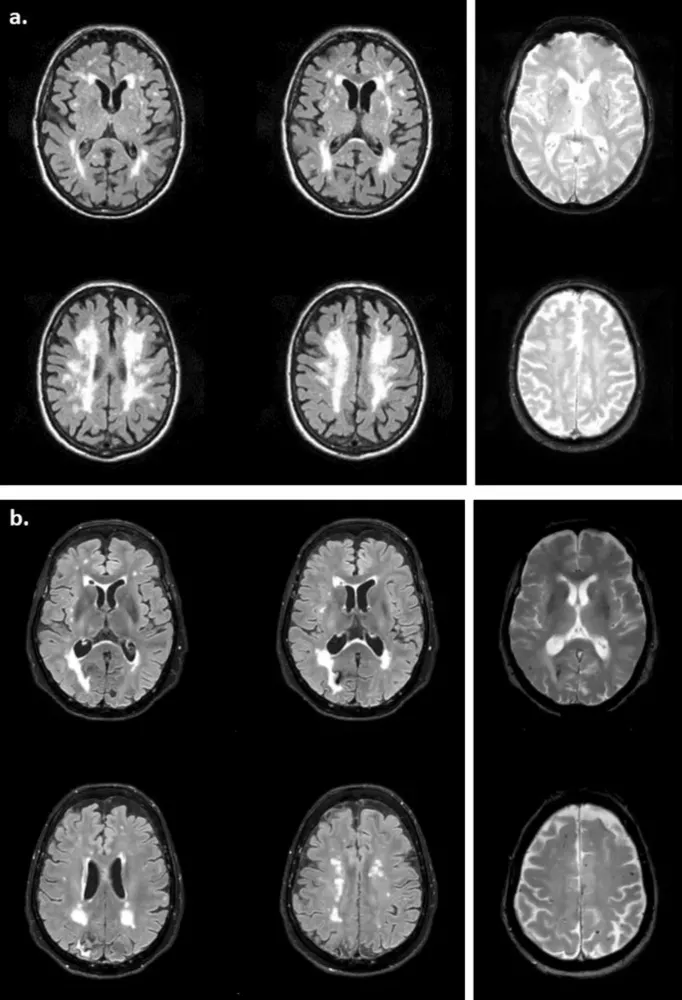

Рисунок 4

Рисунок 1

Рисунок 2

Рисунок 3

Церебральная микроангиопатия (ЦМА) — это группа патологических процессов, поражающих мелкие сосуды головного мозга. Она приводит к таким изменениям, как лейкоареоз (белое вещество гипертензивного генеза), лакуны, микрокровоизлияния и расширенные периваскулярные пространства. Наиболее распространенные формы ЦМА — церебральная амилоидная ангиопатия (ЦАА) и гипертензивная микроангиопатия (ГА).